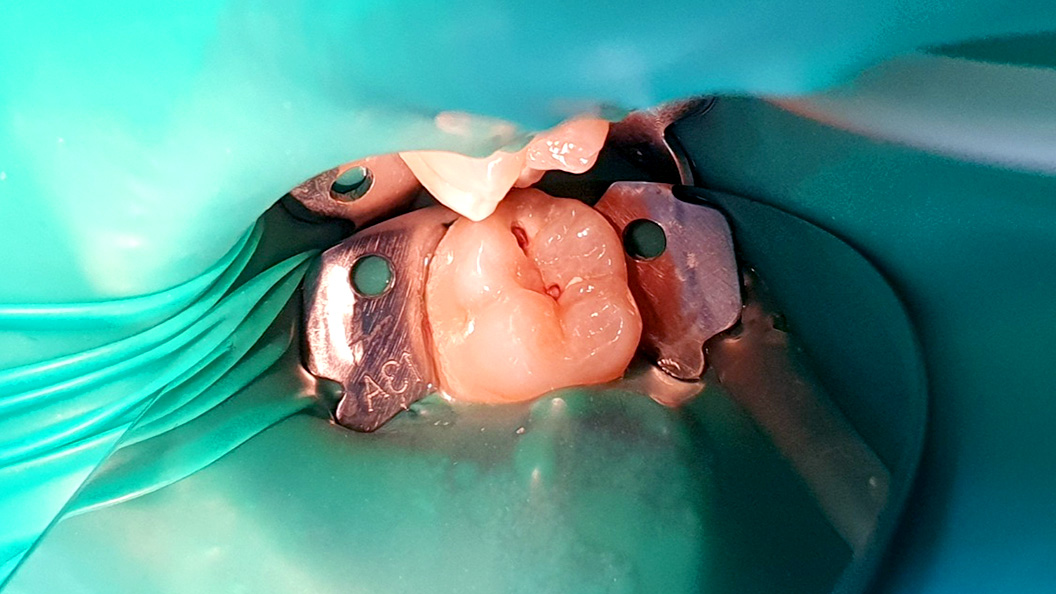

В «Стоматологию Комфорта» обратился пациент с жалобами на наличие кариеса и на боль в области 37 зуба при термическом воздействии. В ходе осмотра врач-стоматолог-терапевт Серебрякова М. Б. поставила диагноз — хронический фиброзный пульпит. Было принято решение о проведении эндодонтического лечения с использованием коффердама для восстановления коронковой части зуба. Врач также рекомендовала дальнейшее восстановление с помощью ортопедической конструкции.

Коффердам представляет собой латексную накладку для изоляции рабочей области от влажной среды. Приспособление значительно облегчает процесс лечения и повышает его качество. Широко применяется в эндодонтической терапии в ходе чистки корневых каналов от инфекции как вспомогательное средство.

- наложение коффердама;